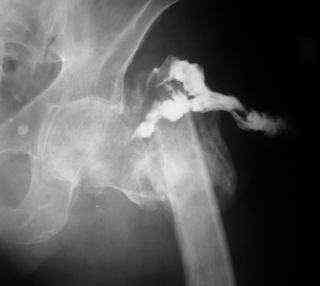

Пациент С., 45 лет, преподаватель одного из ВУЗов г. Москвы, 3 года

назад получил чрезвертельный перелом левой бедренной кости, по-поводу

чего в одной московских больниц лечился методом скелетного вытяжения.

Развилось нагноение в области перелома, после чего имелся свищ по

наружной поверхности бедра (рис. 1 - фистулография). Через 1 год

воспалительный процесс был купирован. Свищ закрылся самостоятельно.